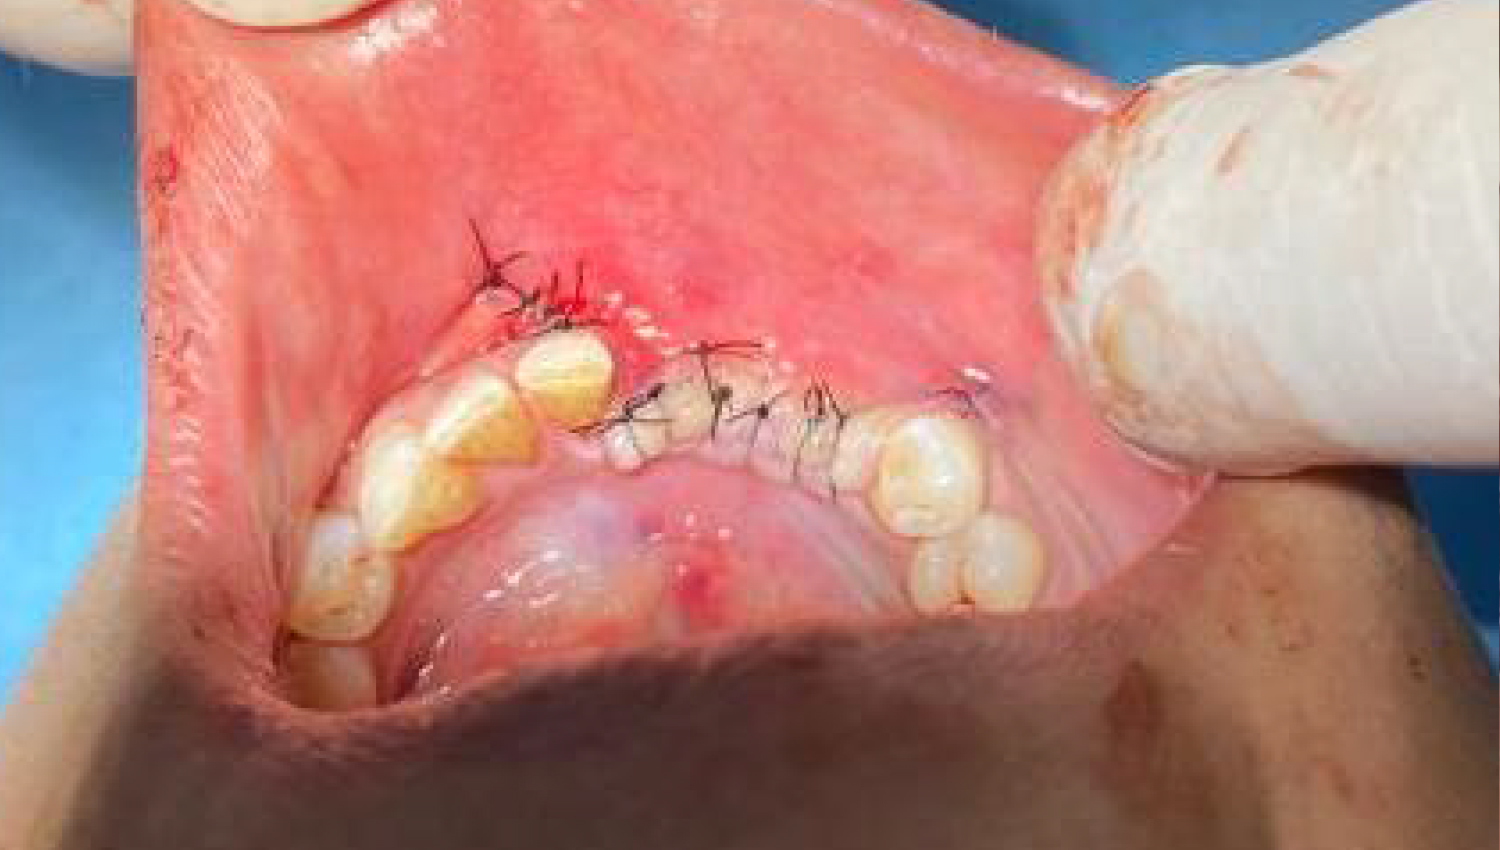

2.Initial clinical view.

5.The operation area was closed after the procedures.